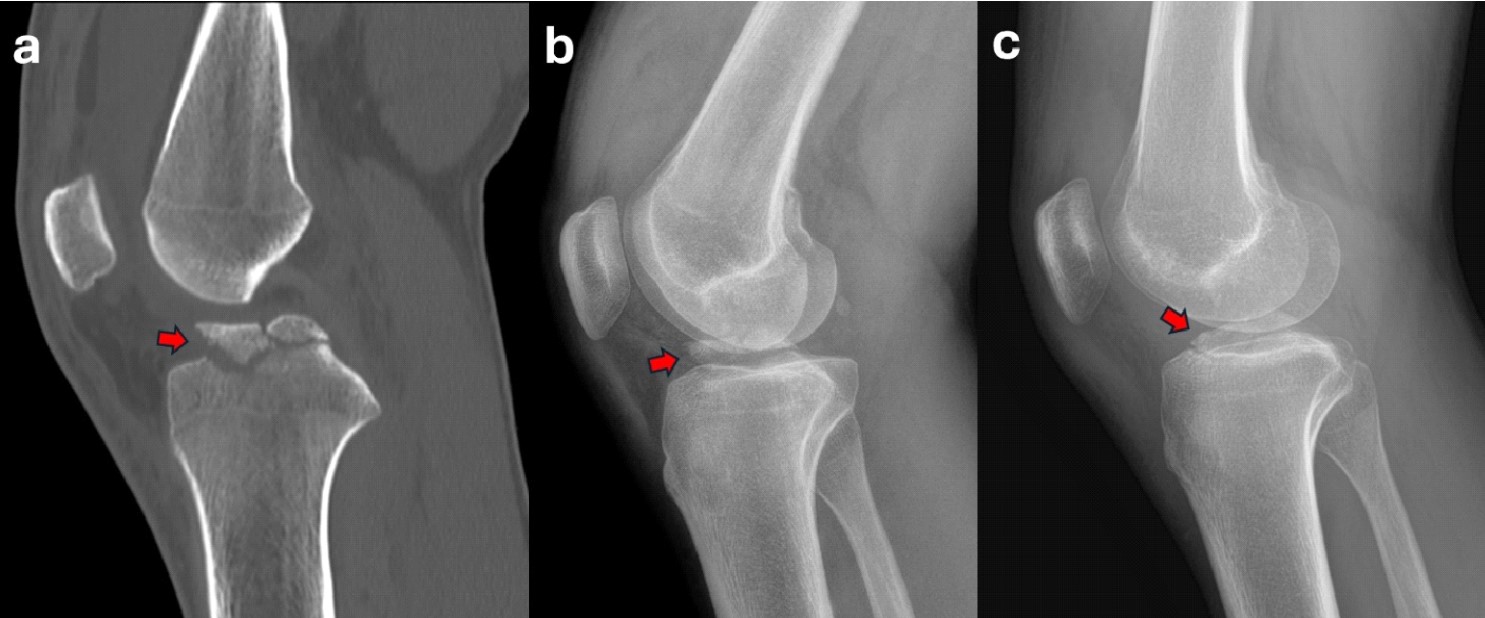

Case 1: A 17-year-old male sustained a right knee sprain during a fall while practicing motocross. The x-ray and CT showed a Meyers and McKeevers Type IV fracture (Figure 12a-b). After ARIF with absorbable sutures performed 5 days after injury, good reduction and healing were obtained at the 6-week follow-up evaluation (Figure 12c), where the patient demonstrated no antero-posterior (AP) laxity and complete range of motion (ROM). The patient returned to non-contact sports 3 months after injury.

Case 2: A 43-year-old male sustained a left knee sprain while skiing. The X-ray and CT showed a Meyers and McKeevers Type III fracture (Figure 13a-b). After ARIF with absorbable sutures performed 7 days after injury, good reduction and healing were obtained at the 6-week follow-up evaluation (Figure 13c), where the patient demonstrated no AP laxity and complete ROM. The patient returned to non-contact sports 3 months after injury.

Figure 12. A 17-year-old male with a Meyers and McKeevers Type IV fracture (red arrow) in sagittal CT scan (a) and lateral radiographs (b). Radiograph at 6-week follow-up showing good reduction and healing of the fragment (red arrow) (c).

Figure 13. A 43-year-old male with a Meyers and McKeevers Type III fracture (red arrow) in sagittal CT scan (a) and lateral radiographs (b). Radiograph at 6-week follow-up showing good reduction and healing of the fragment (red arrow) (c).